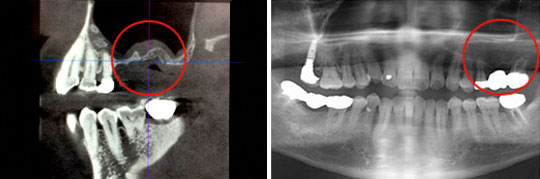

●インプラント(下顎・臼歯)

他院にて埋入したインプラントがグラグラすると悩んでいた患者さんが、当院に来院いただいたケースです。

インプラントがグラグラしており、顎の骨もほとんどない状態でした。

このような難症例の場合、より慎重に診断を行い、CT撮影後に顎モデルの作製を行ってからインプラントの埋入手術を行います。